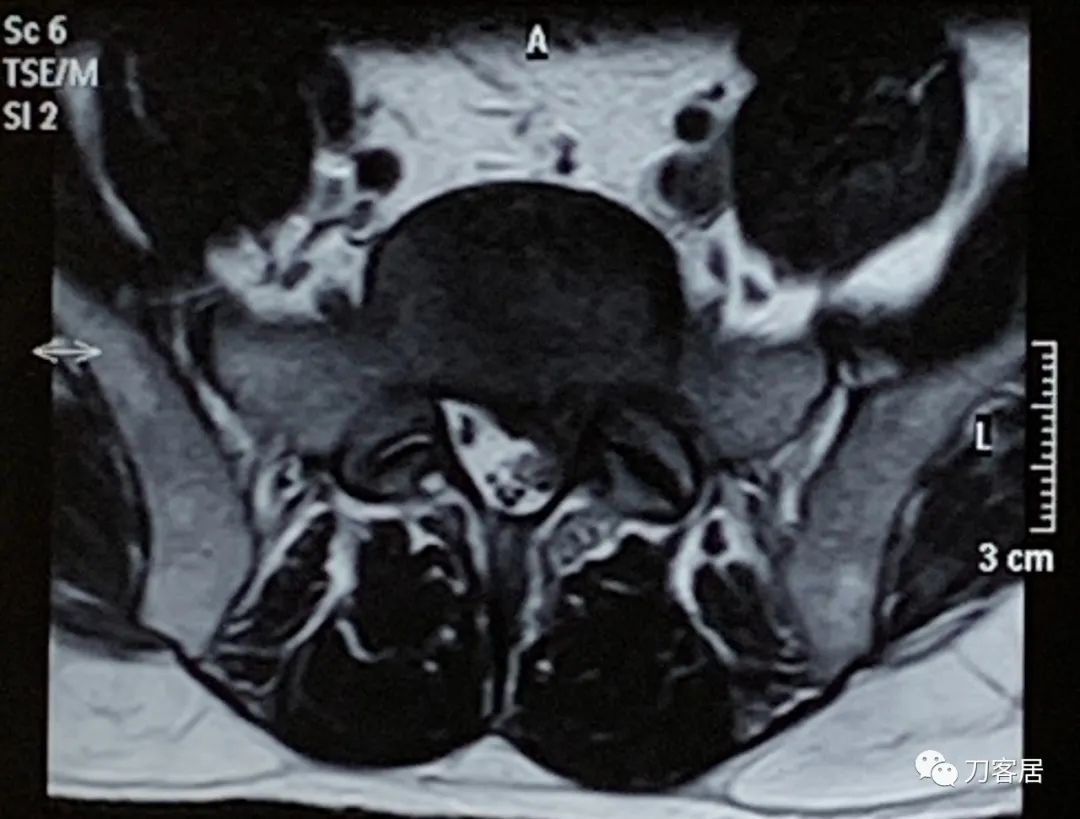

图5. 20220118宁夏医科大学总医院腰椎MRI02,横截面扫描提示腰5骶1椎间盘突出,左旁侧型。

图6. 20220118宁夏医科大学总医院腰椎MRI03,横截面扫描提示腰5骶1椎间盘突出,左旁侧型。